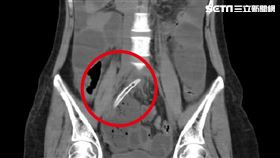

爽吃爌肉 女竟吞「整根牙籤」腸穿孔

38歲的陳小姐4月時,斷斷續續出現肚子痛的情況,直到...